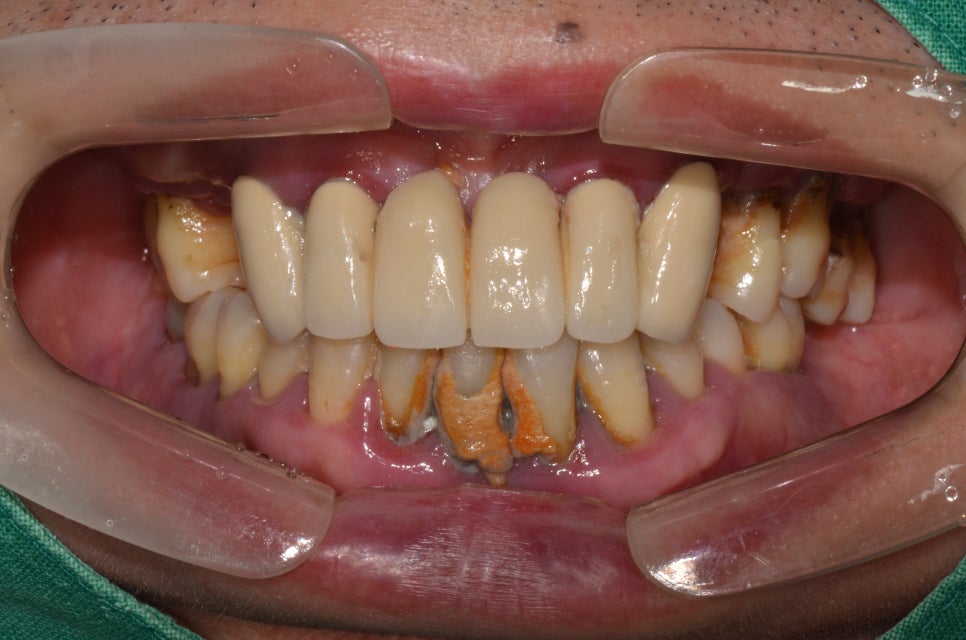

임플란트 치료 전

2020년 6월 16일

내원 이유

50대 남성 환자분이였는데 제목에서 말씀드린 것과 같이 잇몸이 계속 안좋아서 불편함이 있으셨고 이가 빠져서 식사를 하기 힘들다고 명동치과를 찾아 주셨습니다. 해당 환자분께는 임플란트 치료에 대한 자세한 설명을 드리고 치료를 진행하였습니다.

치아 위생상태가 좋지 않아 해당 부분도 같이 치료해 주었습니다. 전악 발치를 진행하고 전악 임플란트를 식립해 주어 치료를 마무리해 주었는데요. 중간에 식사를 잘 하실 수 있도록 임시치아도 해드렸습니다. 현재는 많이 구강 상태가 개선이 되어 잘 사용을 하고 계십니다.